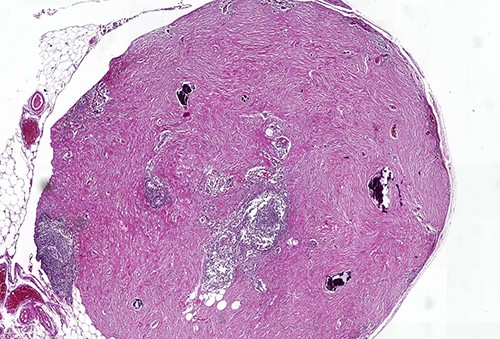

On macroscopic examination, numerous (>100) gray-white-colored grape-like hard nodules were seen, with the largest measuring 4 cm and the smallest measuring 0.2 cm. They were well-circumscribed, unencapsulated, spherical or lobulated and cut surfaces were homogenous, gray-white and firm to rubbery. Microscopically, hypocellular spindle cell proliferations embedded in abundant hyalinized collagen were seen, occasionally dystrophic or psammomatous calcifications interspersed with sparse lymphoplasmacytic infiltrate that may form lymphoid follicles. There was no mitosis, atypia or necrosis (Figs 2 and 3).

Calcifying fibrous tumor with abundant paucicellular hyalinized collagen, interspersed psammomatous or dystrophic calcifications and inflammatory infiltrate consisting of lymphocytes and plasmocytes (H&E, ×4).

In order to distinguish from other spindle cell tumors, immunohistochemical stains were performed. There was positive staining of the spindle cells for Factor XIIIa (Fig. 4) and a diagnosis of CFT was confirmed. Smooth muscle actin, beta-catenin, s-100, CD34, ALK, DOG1 and CD117 were negative; the IgG4/immunoglobulin G (IgG) ratio was 7.24.

Positive staining of spindled tumor cells with Factor XIIIa, ×38.